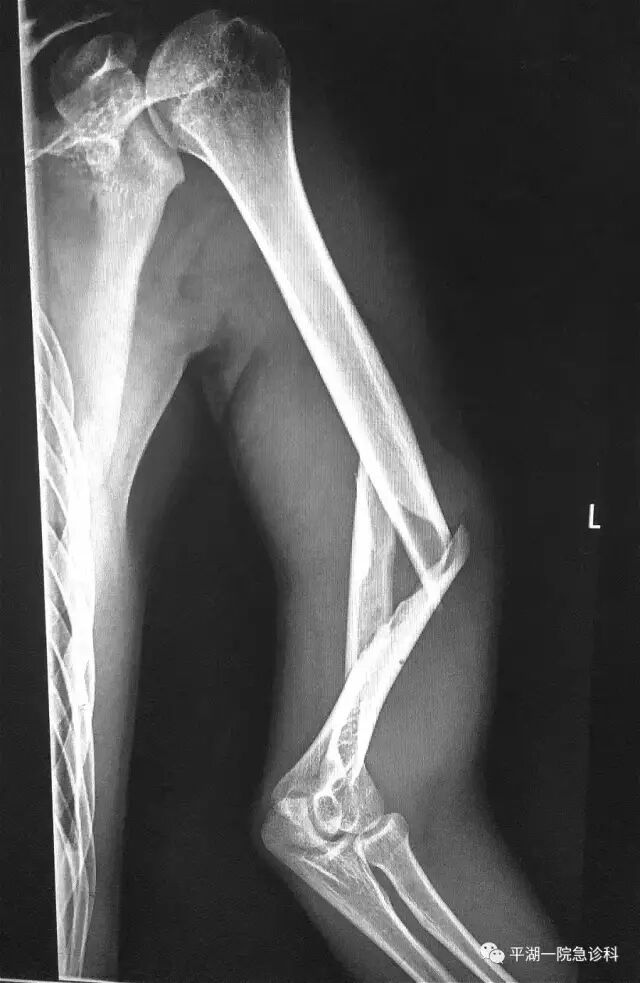

昨晚19:00左右,一位小伙子抱着左臂来看平湖人民医院看急诊,只见小伙子满头大汗,表情痛苦,左臂畸形,左臂碰也碰不得。

小伙子说,因为跟小伙伴掰手腕,猛发力,结果“啪”一声,就这样了!

X线摄片检查:

上臂有个不牢靠的“焊接点”,掰手腕骨折,这种情况确实有可能发生掰手腕所致的骨折多为肱骨骨折,其中以肱骨中下段螺旋形骨折最常见。人的上臂就一根典型的长骨,叫肱骨,在肱骨靠近肘关节上方3~4cm内,有一个圆柱形和不规则扁平骨的结合点,像一个“焊接点”。这个“焊接点”骨质少,比较脆弱,在医学上叫做肱骨髁。我们拎东西时,力量向下,受力方向和肱骨方向一致,肱骨髁可以承受比较大的力量。但掰手腕时,肱骨髁承受的是一种折的力量,医学上称为剪切力。肱骨髁承受剪切力的能力很弱,如果掰手腕时,使力的方向和姿势不对,很容易造成骨折。